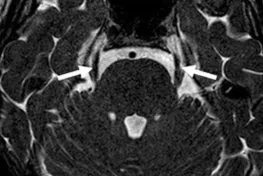

A Steady-state free precession (SSFP) axial image showing the oculomotor nerves (arrows).

A Steady-state free precession (SSFP) axial image showing the trochlear nerves (arrows).

A Steady-state free precession (SSFP) axial image showing the trigeminal nerves (arrows).

A Steady-state free precession (SSFP) axial image showing the abducens nerves (circles).